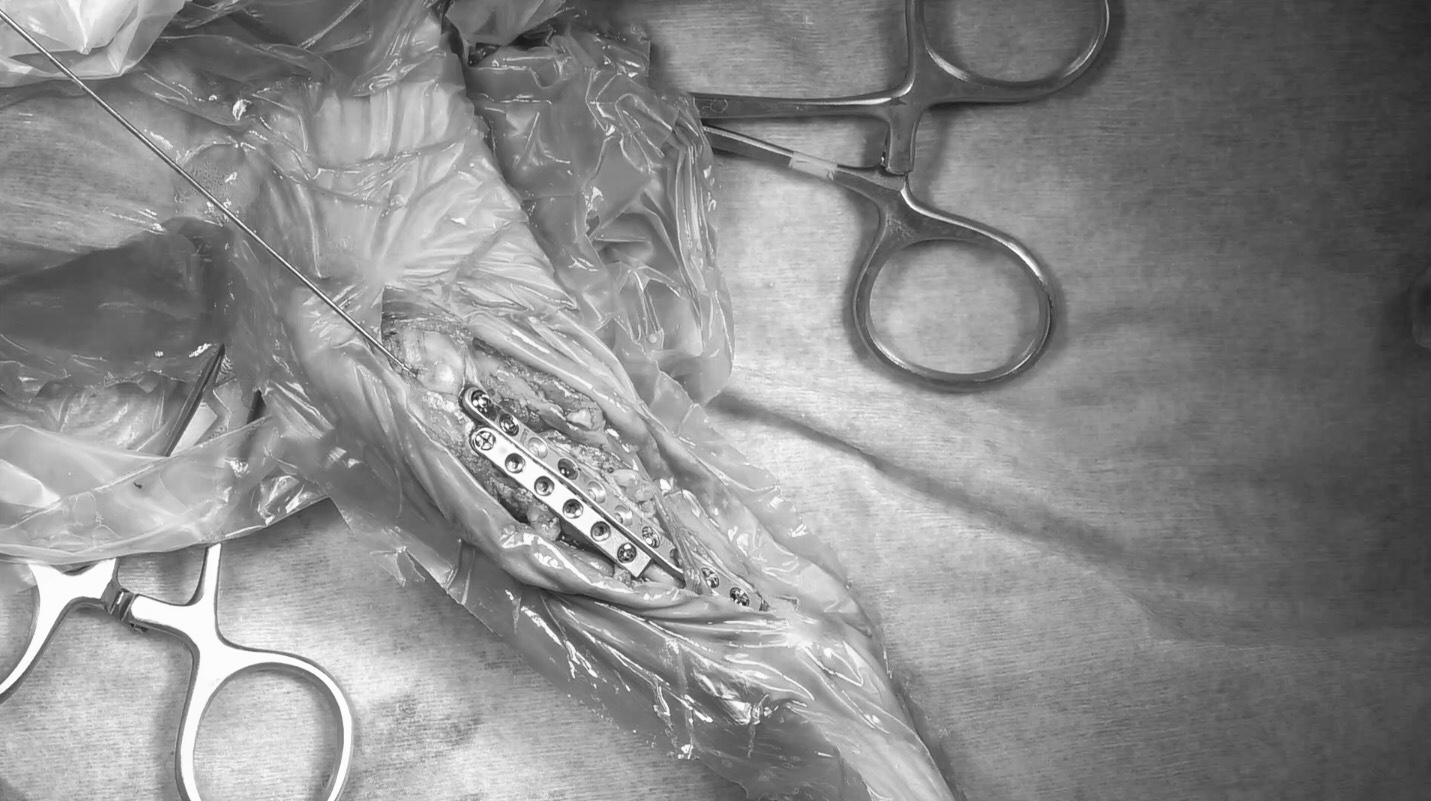

0.8㎜径のK-wireというピンを挿入して骨片の配置を整えた上で、内側面に1.5前内側面に1.3のプレートを設置し固定しました。

術中所見 術前のX線よりも骨折が複雑で骨片が多い印象を受けました